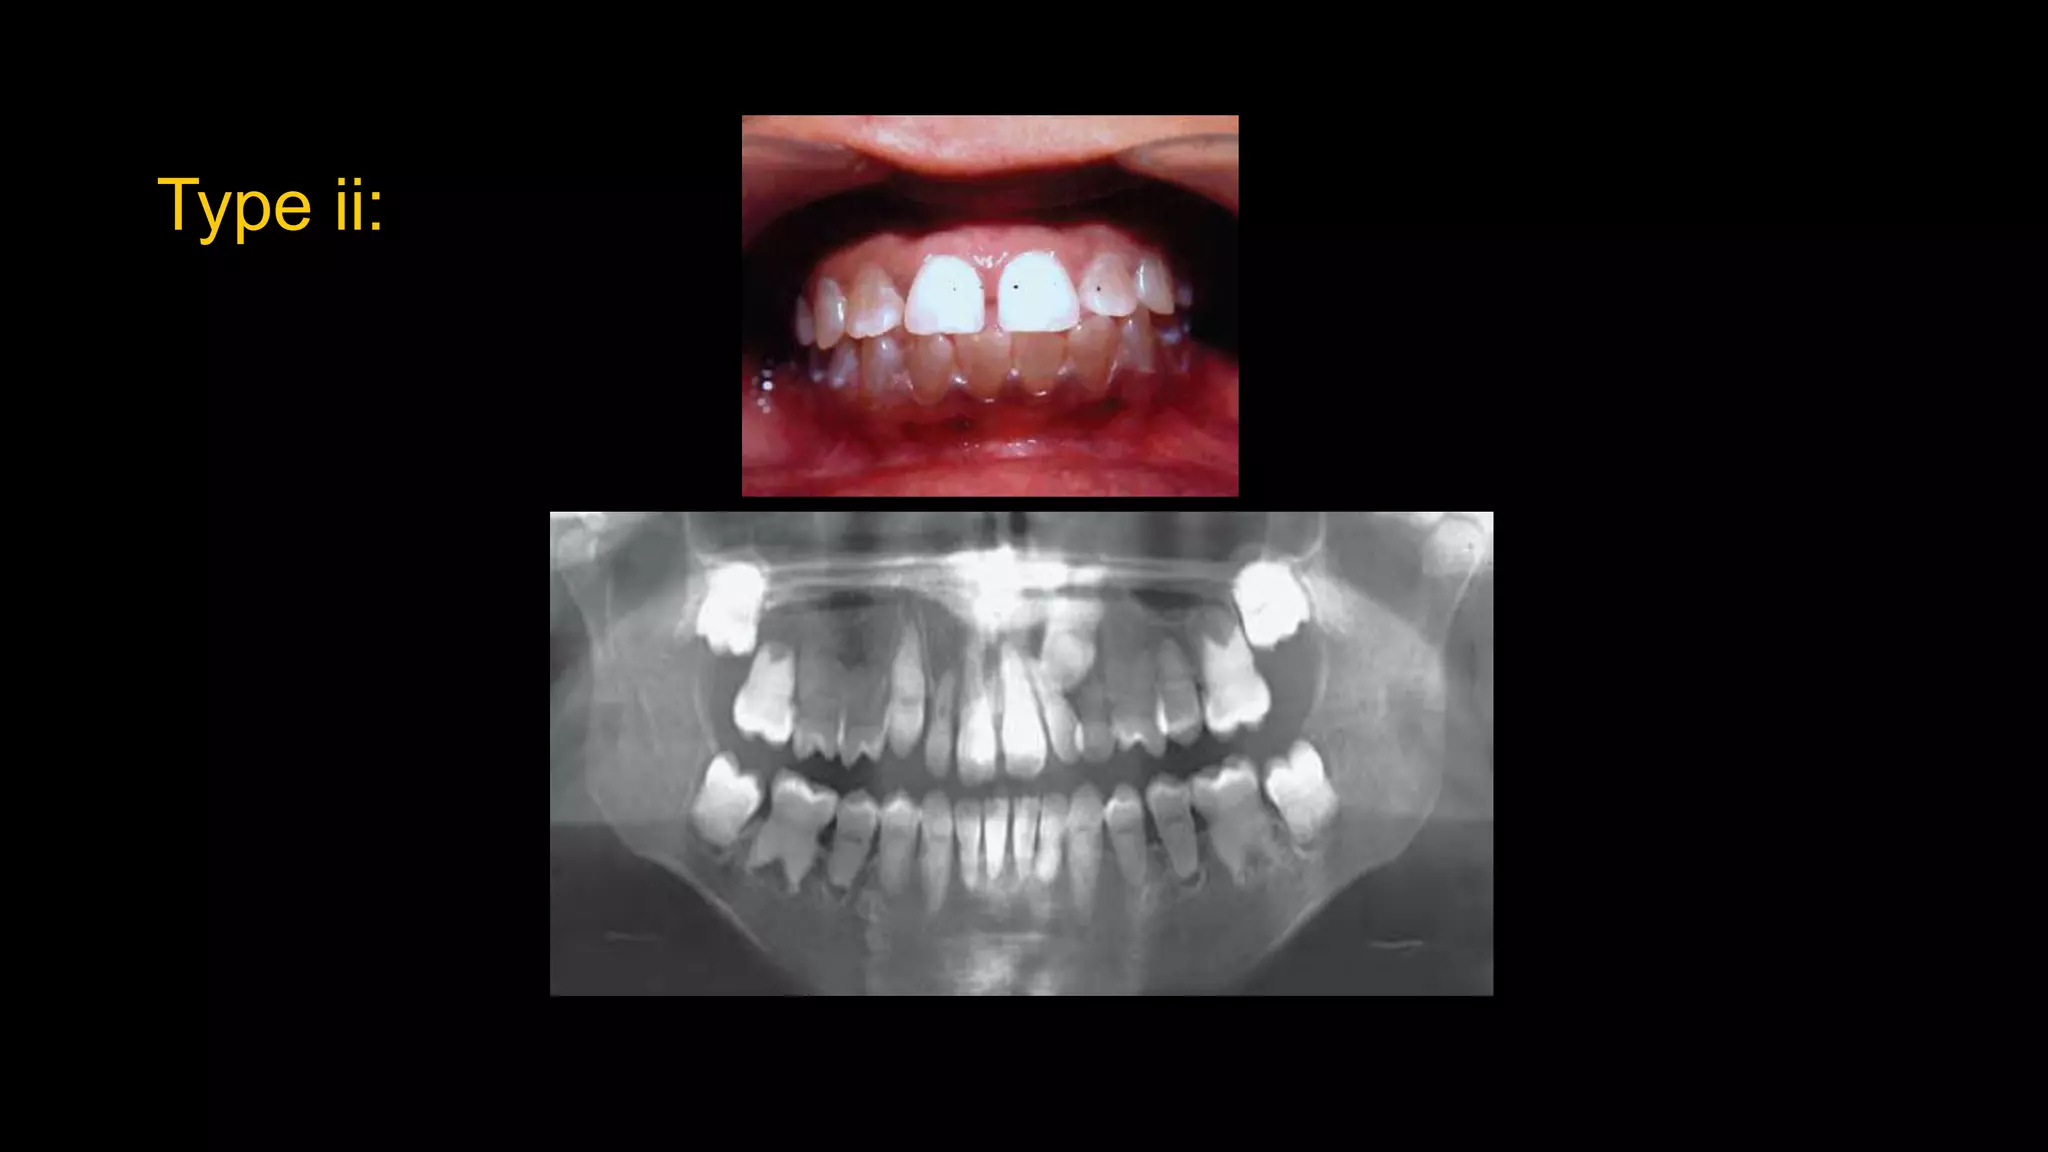

Type ii:

d/d:

• Amelogenesis imperfecta.

• Dentin dysplasia.